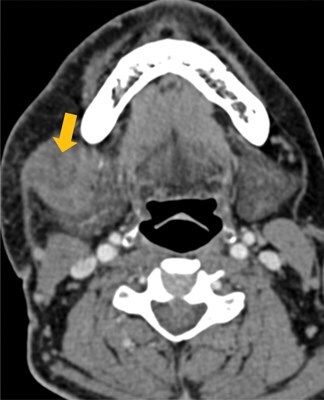

Extranodal extension (ENE) is an established adverse prognostic indicator for head and neck cancers (HNC), and its presence entails adjuvant chemoradiotherapy, hence, it had been incorporated for the first time as the advanced regional node N3b category in the 8th edition of the Union for International Cancer Control (UICC)/American Joint Committee on Cancer (AJCC) Tumour Node Metastasis (TNM) classification for cancers of the oral cavity, human papillomavirus-negative oropharynx, hypopharynx, larynx and major salivary gland carcinomas. Pathological ENE is available for cases which are operated on, but cases which are managed non-surgically or unfit for surgery rely on imaging for providing the information on ENE, and this has prompted researchers across the globe to devise radiological grading for ENE. Radiological ENE has finally been given due credit and incorporated in the 9th version of AJCC TNM staging for nasopharyngeal carcinoma, which came into effect from January 2025. Knowledge of ENE status on baseline imaging prior to operation also helps in counselling patients regarding prognosis and planning adjuvant treatment. In this article, we have comprehensively reviewed the radiological/imaging ENE (rENE/iENE) grading proposed by researchers worldwide, extensively reviewed the existing evidence and challenges of using rENE/iENE for staging, grading, prognosticating and treating HNC, and also discussed the future scope of using rENE/iENE for managing patients with HNC of all the subsites, including thyroid cancers. Artificial intelligence-based studies for predicting rENE/iENE have also been discussed briefly.